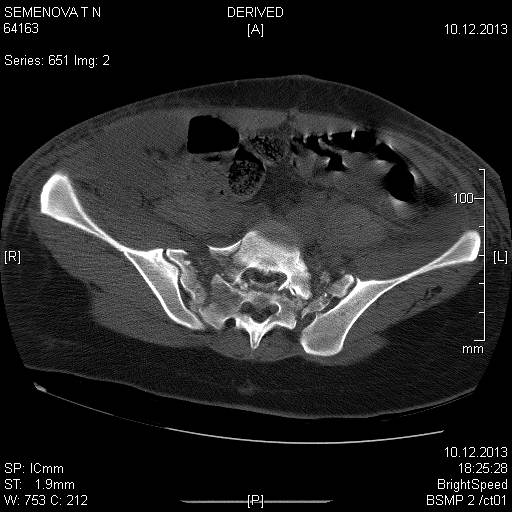

Доброго времени суток коллеги! Прошу вас, подсказать тактику в решении

оперативного лечения следующего сложного повреждения таза. Был ли опыт в

фиксации подобных повреждений?

Травма 03.12.2013,больная переведена из лечебного учреждения соседней

области. На данный момент у больной следующий диагноз: ЗЧМТ,сотрясение

головного мозга;Закр. травма грудной клетки,множественные переломы ребер

справа с повреждением ткани легкого, правосторонний гемопневмоторакс,

состояние после торакоцентеза; Закр.травма живота,разрыв

селезенки,гемоперионеум, состояние после лапаротомиии спленэктомии;

Закр. оскольчатый перелом сред-верх\3 левой бедренной кости, состояние

после накостного металлостеосинтеза; Закр.поперечный переломовывих на

уровне S1S2, многооскольчатый перелом латеральных масс крестца с обеих

сторон,перелом обеих лонных и седалищных костей.

Перелом поперечных отростков L1,L2,L3,L4, L5 позвонка справа. ШОК 3ст.

Вкратце изложил диагноз.